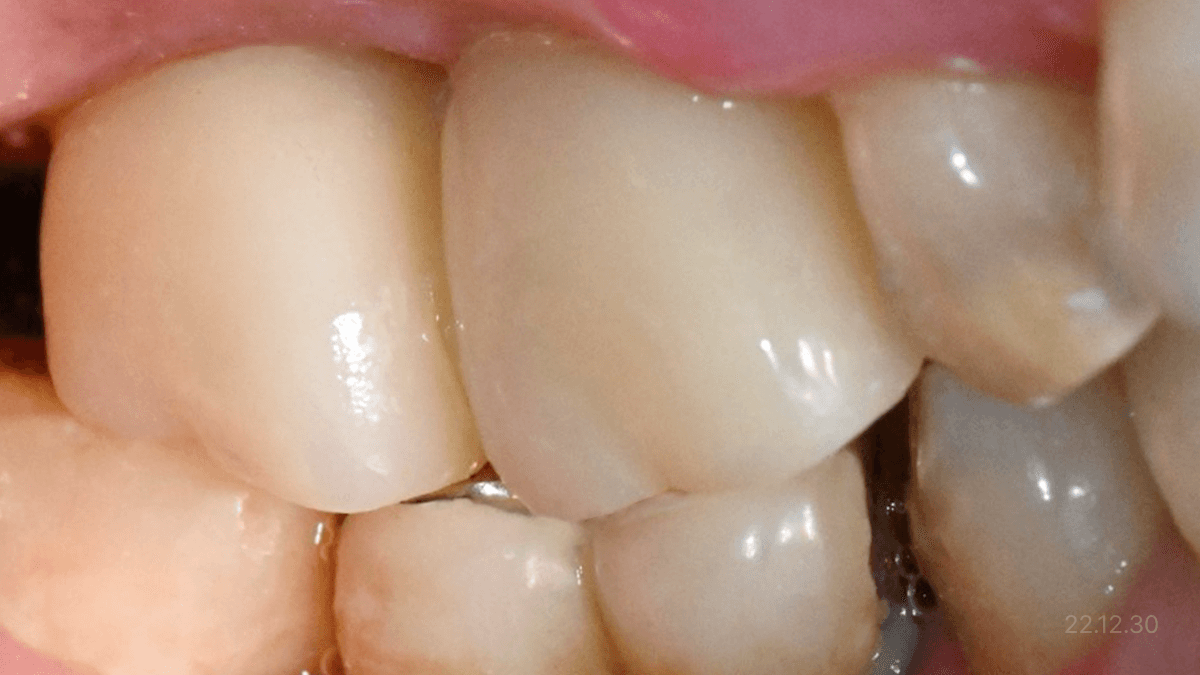

무절개 전용 임플란트 · 절개형 뼈이식 접목

무절개 전용 임플란트 ·

절개형 뼈이식 접목

극심한 잇몸뼈 소실

*위 사진은 환자 본인 동의를 얻어 동일 조건에서 촬영 되었습니다. 모든 치료에는 부작용이 발생할 수가 있습니다.